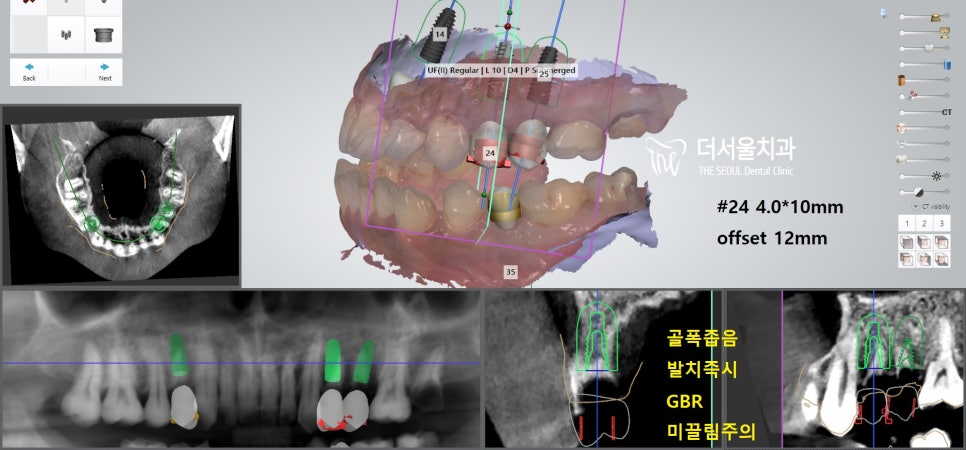

컴퓨터 분석을 이용하여

임플란트가 심어질 위치를 결정한 뒤

본격적인 식립 과정에 들어갔습니다.